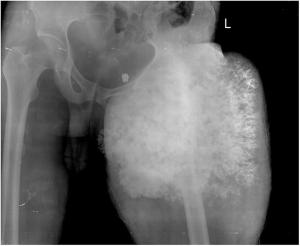

55-year-old male with swelling in left leg for four months.

Case History: Skeletal survey for coarse facial features, short stature, spinal deformity in male child of normal intelligence.